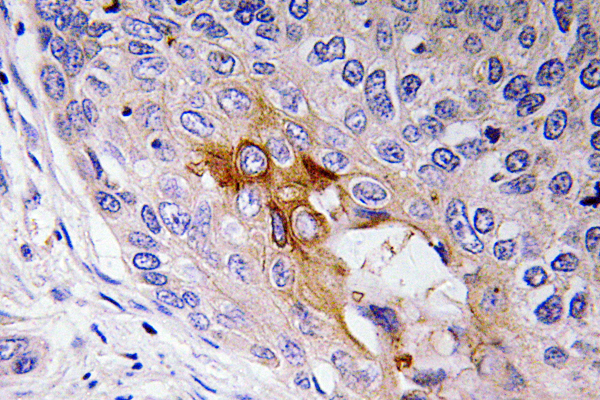

Anti-PEDF AntibodyA97766

ApplicationsELISA, ImmunoHistoChemistry

ReactivityHuman, Mouse, Rat